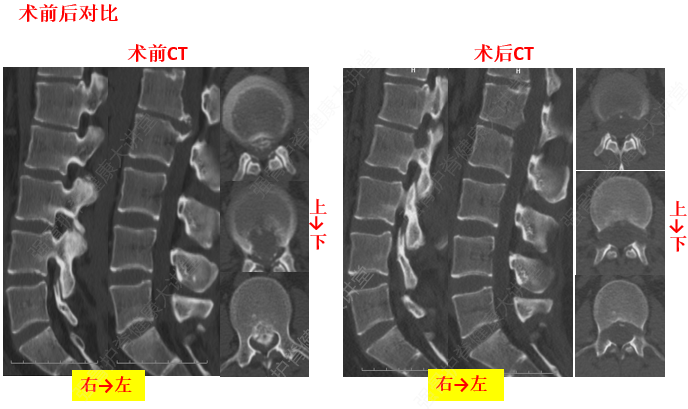

3、椎間盤與椎間韌帶的退變

椎間盤的退變是發(fā)生頸椎病的基礎(chǔ)既是產(chǎn)生本病的內(nèi)因,又是其較為普遍的病理改變。如頸部的長期過度伸、屈活動(dòng)可使弓間韌帶(發(fā)生相應(yīng)的改變)變厚、彈力減弱,甚至發(fā)生鈣化或骨化,直接壓迫脊髓。長期過伸,可損傷前縱韌帶,突然的猛力后伸活動(dòng),可造成前縱韌帶與椎體前緣附著處的撕裂。反之,可造成后縱韌帶損傷或與椎體后緣附著處的撕裂。由于椎間盤的退變,首先出現(xiàn)韌帶松弛,繼而發(fā)生肥厚、鈣化或骨化反應(yīng)。韌帶鈣化部位與椎間盤受損平面相一致。本病患者項(xiàng)韌帶的鈣化是普遍的,可在頸后觸及條索狀物。